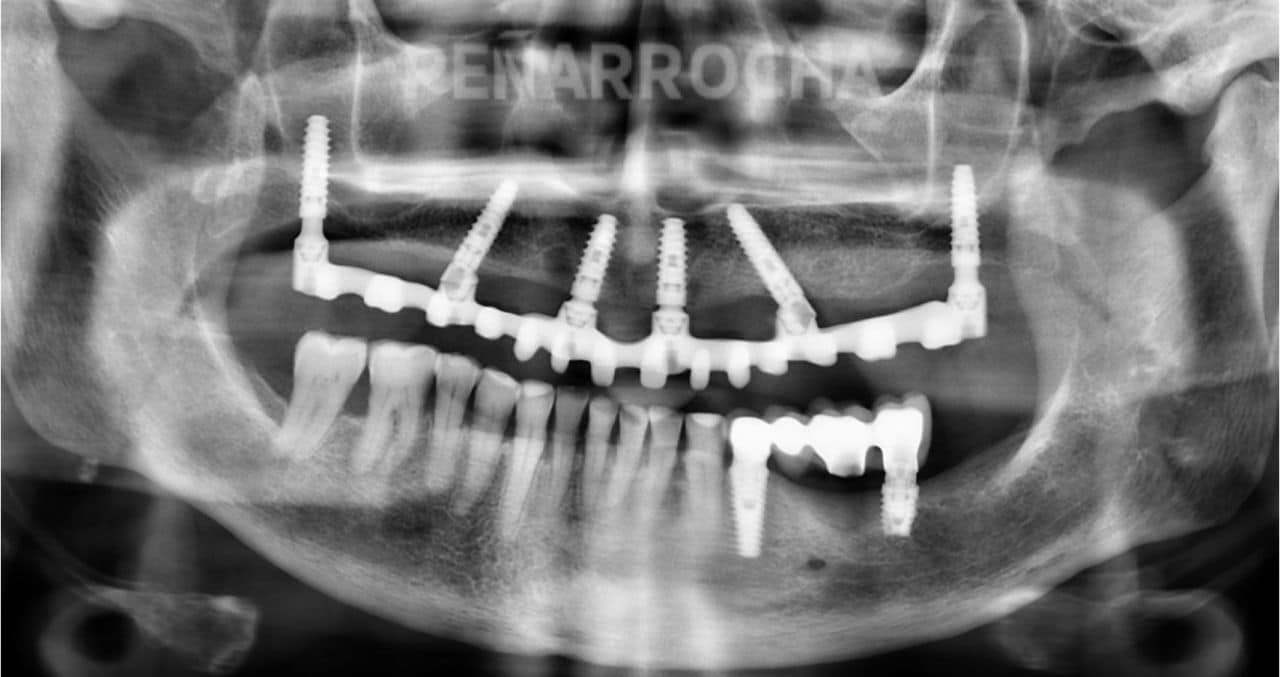

Casos de éxito de implantes dentales con poco hueso en IDIM

En IDIM, contamos con más de 35 años de experiencia tratando casos complejos de implantología dental. A lo largo de nuestra trayectoria hemos logrado recuperar sonrisas de pacientes con condiciones óseas muy complicadas, incluida la falta de hueso suficiente para la colocación de implantes dentales.

Sabemos que la falta de hueso puede ser una preocupación importante, pero gracias a las técnicas avanzadas que utilizamos y a nuestro equipo especializado, hemos logrado devolver a nuestros pacientes no solo una sonrisa estética, sino también una funcionalidad óptima en su boca. Cada paciente es único, y por eso, nos centramos en ofrecer soluciones personalizadas para sus necesidades específicas, teniendo en cuenta la cantidad y calidad del hueso disponible.

Además, entendemos que antes de someterse a un tratamiento tan importante como los implantes dentales, es importante conocer otros casos de pacientes que hayan tenido experiencias satisfactorias. Por eso, a continuación, te compartimos algunos de nuestros casos de éxito más representativos de implantes dentales en pacientes con poco hueso:

Antes:

Después: